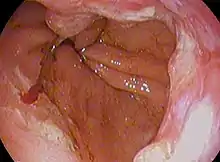

| Endoscopic image of Barrett's esophagus, which is the area of dark reddish-brown mucosa at the base of the esophagus. | |